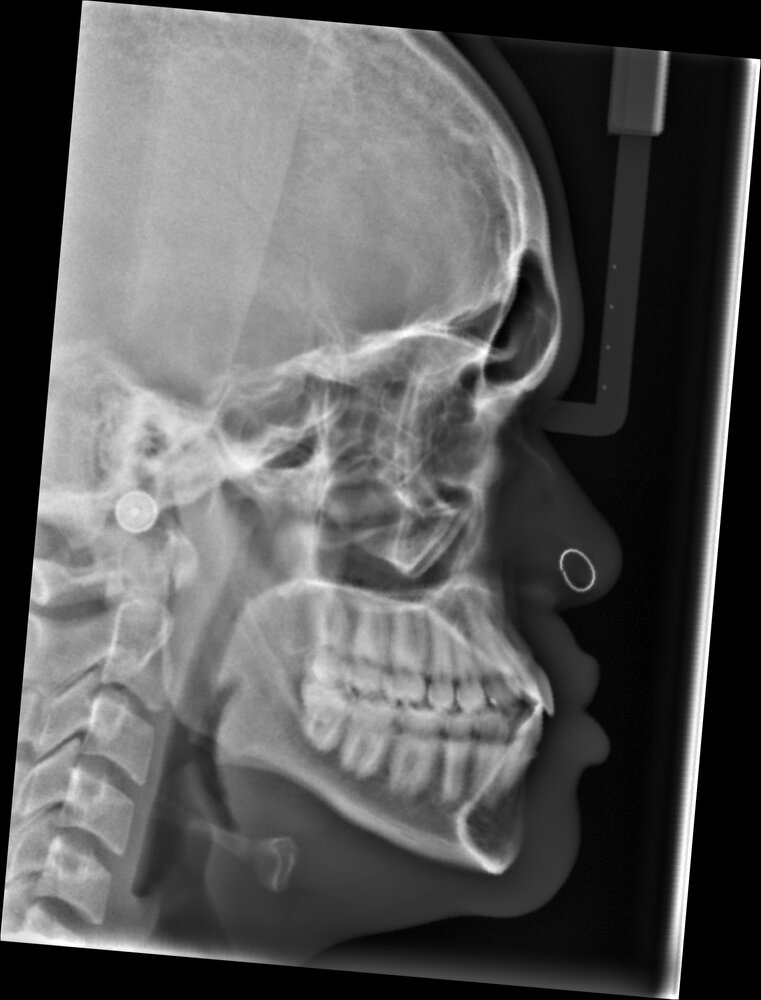

This is an image of a positive and negative orbital vector:

If the orbital vector is negative, it's an indicator that the infra-orbitals rims are recessed. On the other hand, if it's a positive orbital vector, it's an indicator of forward-grown infra-orbital rims.